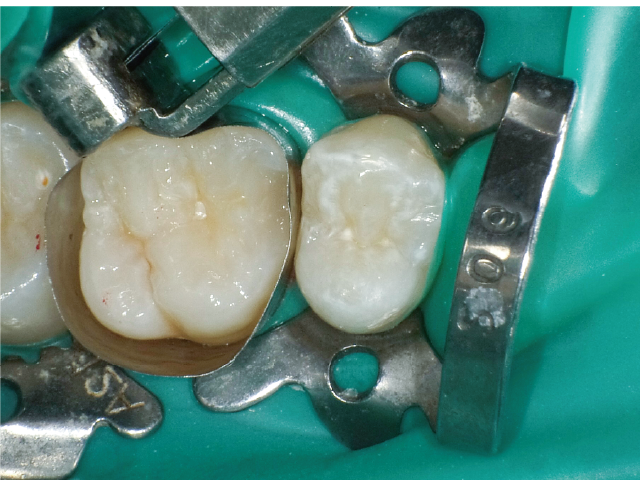

②充填段階(図10~22)

窩洞形成完了後は隣接面部健全歯質の残存範囲によりコンポジットレジンの充填時に用いるマトリックスシステムを選択していきますが、今回はシンプルな操作で設置可能なトッフルマイヤータイプのマトリックスシステムを選びました。隣在歯との距離が小さく、フラットな隣接面形態の再現が必要な症例には最適で、同時に精度の高い窩洞の防湿も可能です。使用したメタルのマトリックスバンドの厚さは30µmと非常に薄く、隣在歯との間に適切な接触関係を回復することができます。

接着操作には窩縁部エナメル質へのセレクティブエッチングに続いて、2ステップタイプのセルフエッチングシステム(クリアフィル® メガボンド®2 : クラレノリタケデンタル)を使用し、フロアブルレジンとペーストタイプレジンとを併用したシンプルな積層充填操作により隣接面形態を回復しました。

本症例では窩洞底部のエナメル質窩縁への窩洞形成の最終仕上げに硬組織の繊細な切削が可能なエアースケーラーチップを活用し不用意な窩洞規模の拡大を防ぐことができました。それにより、シンプルなマトリックスシステムでの隣接面部への精密な充填操作が可能となり、修復の長期予後に期待がもてる状況となりました。精度の高いMIコンポジットレジン修復において、エアースケーラー専用のダイヤモンドチップが非常に相性が良いことが確認されました。このような切削システムを有効に活用することで、より精密で長期的な修復結果が得られる可能性が高いと考えます。